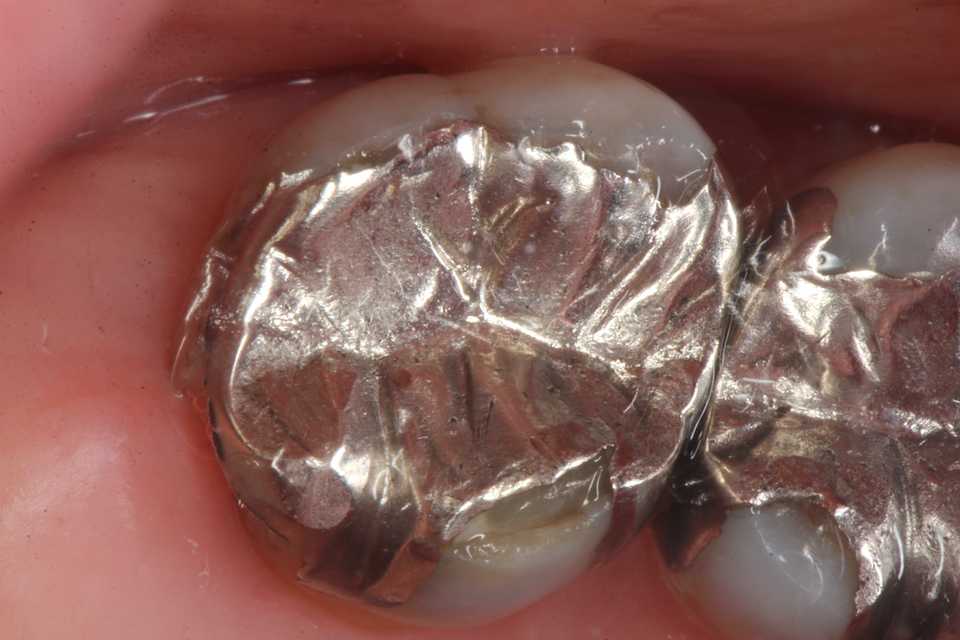

50代女性、左上5-7ブリッジ脱離、7番2次カリエス+Per(根尖性歯周炎)、強度の外傷性咬合この方、ひどい食いしばりで歯が壊れてしまう。噛み合わせの左下7番も歯冠が崩壊しつつある。7番はブリッジが脱離していて、内部は虫歯でドロドロ。Perつまり根管充填が緊密ではなく、歯根内部は細菌だらけで根の周りにはひどい炎症がある。まずはレントゲン写真から。7番の歯根の周りが炎症で黒くなっているのが分かると思う。ブリッジを全部外すと咬合が狂うので、とりあえず7番だけカットして内部を見てみた。根管充填材が見えるところまで軟化象牙質を除去して、3MIX+α-TCPを入れて根管内部を殺菌することにした。根管充填材の周りは黒くなっているのが見えると思うが、これは硫酸塩還元細菌の代謝産物の硫化鉄:FeSで、理想に反して根管充填材はゆるゆるの緊密充填ではないことを示している。このような状況は普通のことだ。歯根内部は細菌だらけということだが、ゆるゆるだから根管充填材を全部除去する必要もない。ゆるゆるの隙間から3MIX(抗菌剤)は浸透し根管は殺菌される。外傷力を弱めるために咬合調整を繰り返している。コア部分は隙間に細菌由来の黒色物質FeSがこびりつき、真っ黒。ポンティック下も細菌のコロニーでドロドロ歯質は残っているように見えるかもしれないが、ボンディング材が効く程度に軟化象牙質(虫歯)を除去すると、残根状態になる。つまり通常治療では抜歯しかないということだ。しかもPerでグラグラの動揺度2〜3、垂直性同様有りだ。とてもこのままではブリッジの支台には使えそうもない。ピンク色の根管充填材が見えると思うが、周りは真っ黒だ。その真っ黒になった隙間から細菌は侵入するし、3MIXも浸透する。こうではない緊密な根管充填治療は垂直加圧法でしか見られない。3MIX+α-TCPCR(ダイレクトボンディング)で覆う。これでないと微小漏洩が起こり失敗する。丸い形はラウンデッド・コアと呼び、この形が咬合力を内向きに集中させ歯根を守る。ポストは歯根の外側にこじるような応力を生じるので歯根を壊してしまいやすい。補綴物が必要な時はピンレッジで維持力を得る。これはCAD/CAMでは作れないだろう。これで2〜3週間様子をみる。外傷性咬合のコントロール(ナイトガードや行動療法)をしながら。つづく